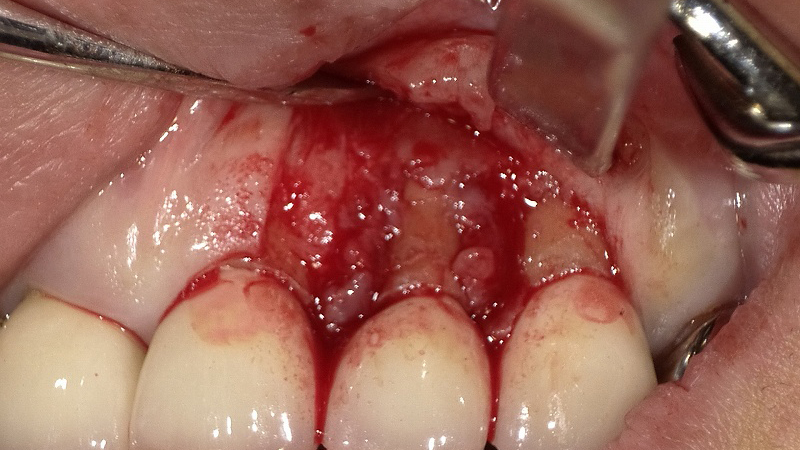

下記の口腔内写真(下顎大臼歯部)に対する歯周外科手術(フラップ手術)の様子です。

🦷 口腔内写真の解説

本写真は、下顎右側第1・第2大臼歯(6番・7番)部の歯周外科処置時の所見を示しています。

歯肉弁を剥離し、骨縁下の病変部が明示されています。

- 下顎第2大臼歯(7番)

骨縁下ポケットが深く、歯根分岐部にまで炎症が波及しています(矢印部)。分岐部骨吸収が明瞭で、プラークや歯石が沈着していた痕跡が認められます。分岐部病変(Class II〜III相当)が存在し、保存的治療のみでは治癒が困難な状態と考えられます。 - 下顎第1大臼歯(6番)

骨縁下ポケットは7番よりも浅く、中等度の骨吸収を認めます。隣在歯7番の慢性炎症の影響を受け、遠心部の骨吸収が進行しています。

本症例では、**歯肉剥離掻爬術(フラップ手術)**により、深いポケットおよび分岐部病変部の肉芽組織を除去し、ルートプレーニングを行うことで、清掃性と治癒環境の改善を図っています。術後は骨再生材料やリグロス等の応用も検討されるケースです。

歯肉の切開剥離

写真は表面麻酔後、浸潤麻酔をして上顎1番中央部から3番の遠心部にかけてメスで歯肉を切開し、骨膜剥離子で歯肉剥離して骨面を露出させた所です。上顎2番(側切歯)の近心及び遠心に大量の不良肉芽(ふりょうにくげ)組織が認められます。